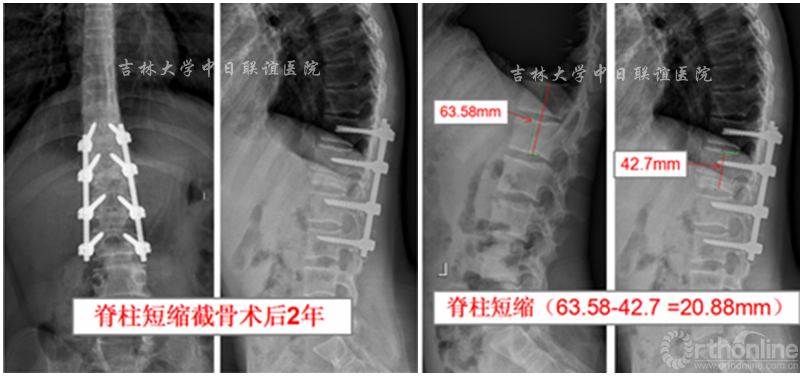

脊柱短缩截骨术后影像学检查:

脊柱短缩截骨术后1年后行双足畸形矫形术:术后1年,患者双下肢感觉、肌力明显好转。一期右足行皮肤软组织松解覆盖创面3月后二期行矫形手术治疗。